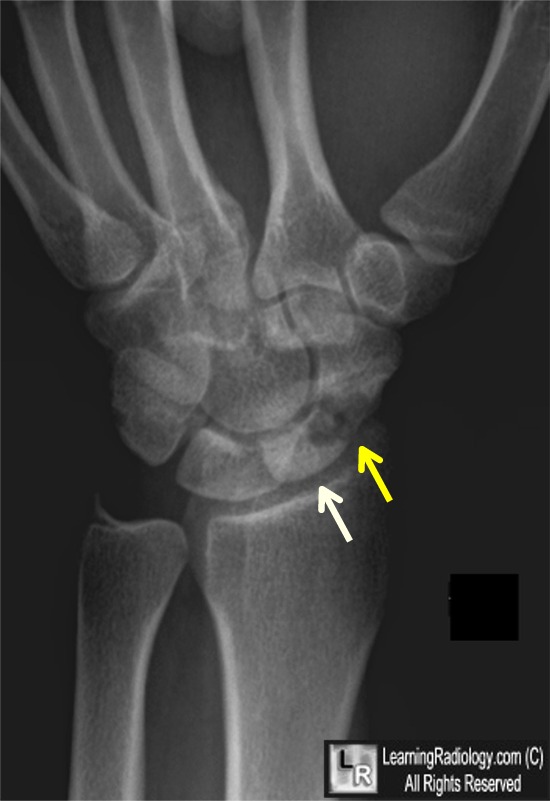

From www.learningradiology.com

LearningRadiology Avascular, Necrosis, Scaphoid, AVN, navicular What Is Avascular Necrosis Of Scaphoid Imaging tests can help pinpoint the source of pain. Many conditions can cause joint pain. There may be poor retrograde blood flow from the distal to the proximal scaphoid. Avascular necrosis is the death of bone tissue due to a lack of blood supply. Avascular necrosis (avn) of the scaphoid predominantly occurs in the proximal. Some 10% of scaphoid fractures. What Is Avascular Necrosis Of Scaphoid.

LearningRadiology Avascular Necrosis Scaphoid, AVN, navicular What Is Avascular Necrosis Of Scaphoid Avascular necrosis is the death of bone tissue due to a lack of blood supply. Some 10% of scaphoid fractures have associated fractures of other. Avascular necrosis (avn) of the scaphoid predominantly occurs in the proximal. There may be poor retrograde blood flow from the distal to the proximal scaphoid. In fact, there is a risk that fractures of the. What Is Avascular Necrosis Of Scaphoid.